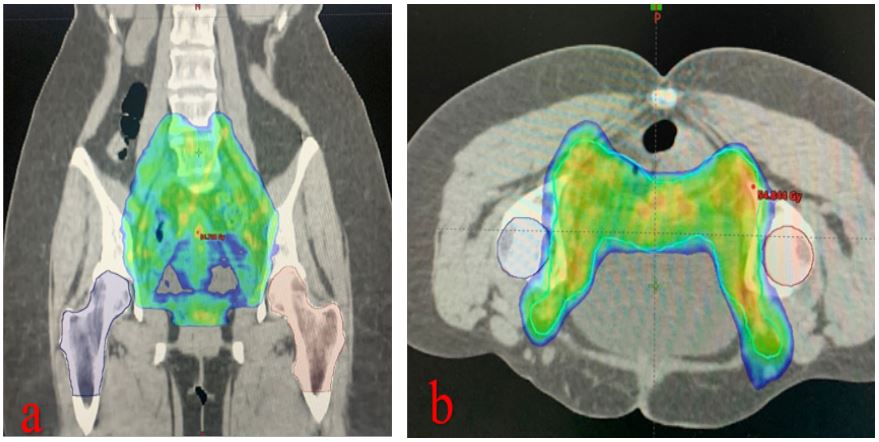

A 47-years-old woman with FIGO stage 3 C1 cervical cancer applied to our clinic in August 2019. She was treated with 50,4 Gy pelvic external beam radiotherapy (EBRT) using the volumetric arc therapy (VMAT) technique with chemotherapy (cisplatin, total 5 cycles of 40 mg/m2 /week). It was followed by 30 Gy intracavitary radiotherapy prescribed to HR-CTV (6 Gy per fraction; once a week). A complete response was achieved three months after. During regular follow-up, 12 months after treatment, the patient complained of pain in her hip and groin. The pain was intensified with movement. In her anamnesis, there was no previous history of trauma or fall. She was a non-smoker, non-diabetic, and non-obese (Body Mass Index: 23.8). She didn’t have any comorbidities. On physical examination, there was a bilateral limitation of motion in hip joints, but there was no visible swelling or redness. Also, the FABER test was positive. The magnetic resonance imaging (MRI) showed a crescent sign and a fissure with bone marrow edema on the bilateral femoral heads (Figure 1). In EBRT treatment plan, only 5% of the bilateral femoral head volume received a dose above 42 Gy. However, the maximum point doses of the right and left femoral heads were found to be 51.3 and 49.4 Gy, respectively. Coronal and axial plan dose distributions of the femur heads are shown in (Figure 2). Considering the patient’s radiotherapy history, imaging findings, and physical examination findings, the patient was diagnosed with bilateral AVN of the femoral head. She was referred to an orthopedic clinic and was advised to undergo bilateral hip arthroplasty. She refused the operation and received conservative NSID and physical therapy. The patient was completely relieved with rest and this regimen. Follow-up MRI at 3- months showed regression of the bone marrow edema on bilateral femoral heads, but the persistence of fissure lines was consistent with AVN. After 1- year, the patient was pain-free and had no difficulty in walking.

Figure 2: Dose distribution of 50,4 Gy around the femoral head area. (a) coronal plan (b) axial plan.